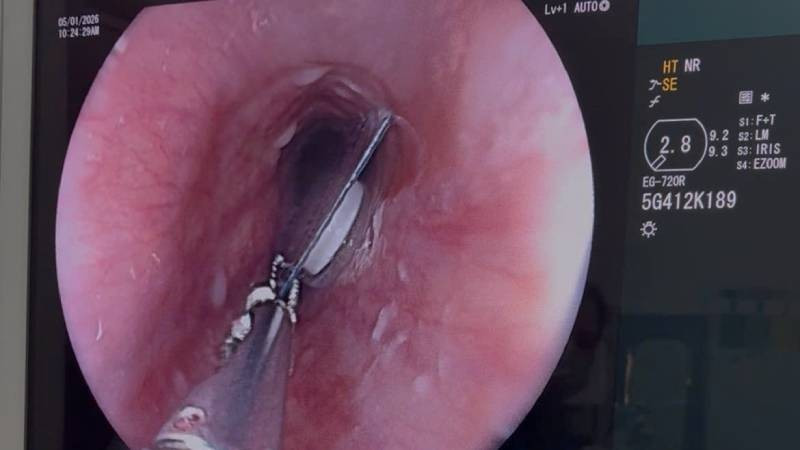

Bên cạnh đó, nhờ có nguồn máu an toàn và chất lượng, còn giúp cho ngành Y tế có thể triển khai, áp dụng nhiều kỹ thuật mới hiện đại như: ghép tạng, ghép tế bào gốc.